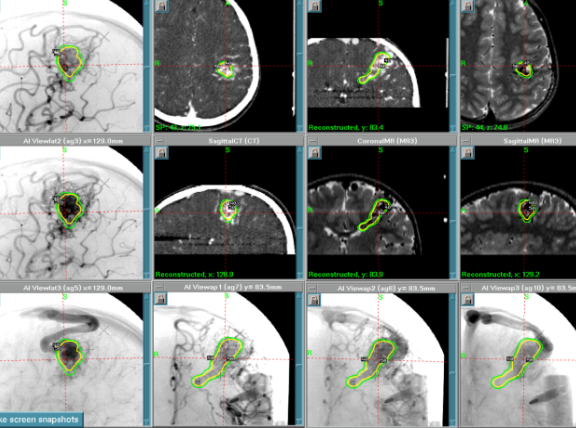

脳動静脈奇形に対するガンマナイフ治療計画(図1)

(各球状照射野を腫瘍のみに配置し、脳への過照射を避ける)

当科では、安全第一を掲げており、大きさに関わらず「導出静脈=ナイダス移行部をターゲットとし、照射体積4ccに対し辺縁線量22グレイ」を基本に行い、一度もしくは必要であれば段階的治療を戦略で行っております(図1)。無理なく安全に完治へと向かわせたいと考えております。